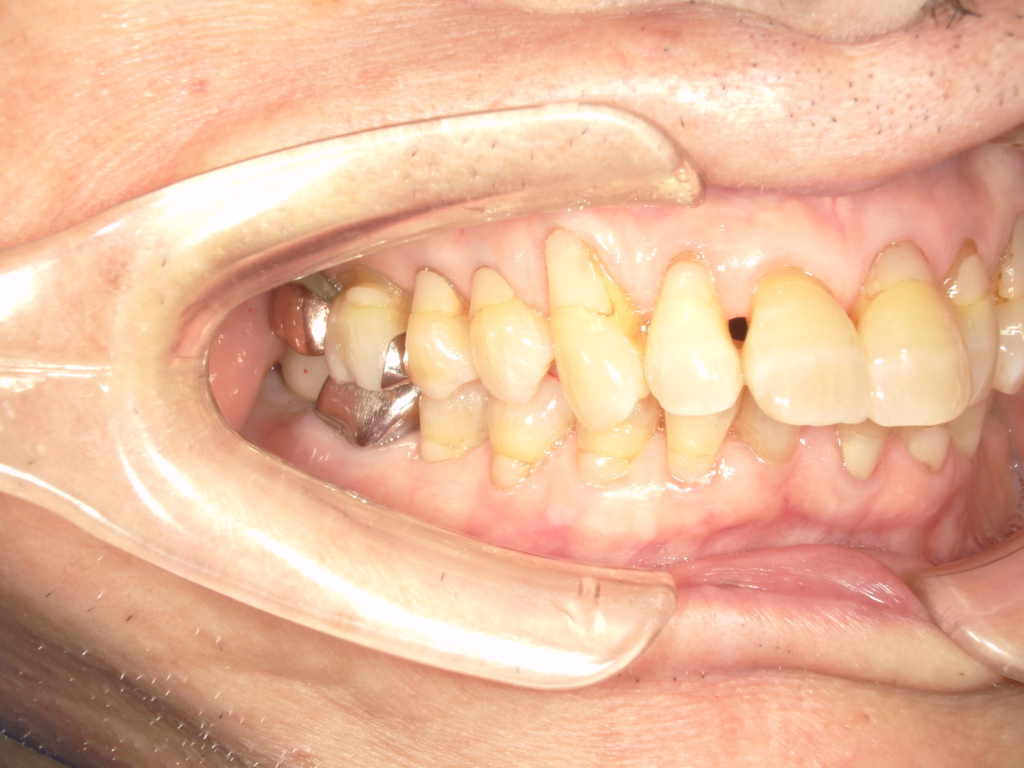

前歯の4本が、残すのが難しい状況となり、インプラント治療を行いました。

インプラントは前歯に2本埋入し、4本の前歯を作っています。歯を抜くと同時にインプラントを埋入し、仮歯を作りました。その後2ヶ月で、被せ物を入れました。被せ物は、セラミックスで作っています。

治療前

治療後